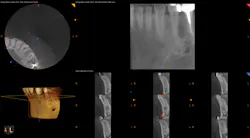

To determine whether tooth No. 21 or No. 22 was the issue, two periapical radiographs were taken. However, the results were inconclusive (figures 2–4). With clinical testing and 2-D radiographs providing no smoking gun, it was decided to use limited field-of-view CBCT (Carestream Dental CS 9000C 3D) on the region. CBCT revealed that tooth No. 22 was abscessed and a fair amount of the apical bone was completely gone (figures 5 and 6). In fact, since the time the pain began and when the patient presented at the practice, the tooth had abscessed at an alarming rate and was now considered an emergency situation.

Figure 5: CBCT showing the periapical lesion on No. 22 in multiple slices on the lower right-hand side of the image

Figure 6: CBCT showing a single view of the periapical lesion in the lower right of the screenshot